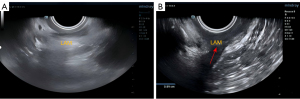

Linear measurements were performed by transperineal 2D ultrasonography. The initial plane was the midsagittal plane of the pelvic cavity, and the probe (DE10-3WU, harmonic frequency 3.0–9.0, gain setting 50, imaging depth 4.0, frame rate 45) was traced along the direction of the bilateral LAM to the attachment of the inferior pubic ramus. If there was a discontinuity between the hyperechoic fibers and the pelvic lateral wall and the insertion was replaced by an abnormal echo area, LAM injury or avulsion was diagnosed. The width of the injury was measured (Figure 1).

The abdominal volume probe (SD 8-1U) under transperineal guidance was used to obtain the standard median sagittal section of the pelvic floor, with the indicator point facing the ventral side of the patient and the direction of the sound beam parallel to the sagittal plane of the human body (6,7). For imaging analysis, a single optimal frame demonstrating the maximal descent during the most effective Valsalva trial was captured and stored for offline measurements. According to the “Chinese Expert Consensus on Pelvic Floor Ultrasonography (2022 edition)”, the degree of POP was determined in the maximum Valsalva position. The lowest point of the posterior bladder wall or the junction between the bladder neck and urethra was taken as the landmark structure of anterior pelvic prolapse, and the lowest point of the cervix was taken as the landmark structure of middle pelvic prolapse.

Points above the reference line were designated negative, and those below the reference line were defined as positive. The degree of POP was determined according to the distance between the lowest point of pelvic organs and the posterior-inferior edge of the pubic symphysis in Valsalva maneuver. Combined with clinical studies using pelvic floor ultrasound to quantify POP, the degree of POP was divided into three degrees, anterior pelvic: The lowest point of bladder neck or posterior bladder wall below the pubic symphysis line was defined as mild (0–10 mm), moderate (11–25 mm), and severe (>25 mm).

In the middle pelvis, the cervical nadir was defined as mild when it was 0–15 mm above the pubic symphysis line, moderate when it was 0–20 mm below the pubic symphysis line, and severe when it was greater than 20 mm. The range of motion of the bladder neck was calculated according to the difference in distance between the bladder neck and the reference line at rest and after Valsalva maneuver (Figure 2).